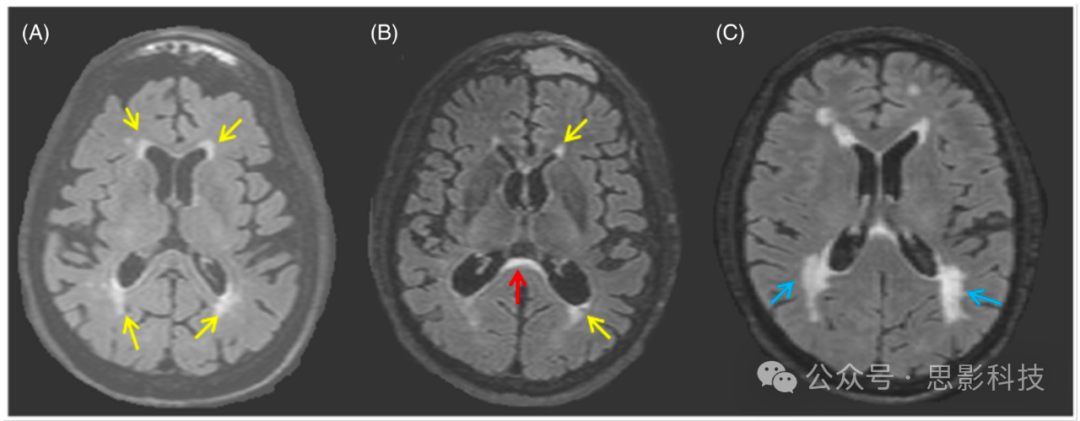

WMH 通常定义为在 T2 FLAIR(fluid-attenuated inversion recovery)及 T2 加权 MRI 上呈高信号,而在 T1 加权上表现为等信号或低信号(其中 T1 低信号往往提示更严重的病灶;见图 1)。WMH 被视为“可见的”白质损伤,可呈局灶、多灶或融合性(见图 1),在严重阶段可累及大范围白质。WMH 并非特异于某一种疾病,导致白质损伤的多种原因均可在 MRI 上呈现为 WMH。然而在老年人中,WMH 一般被认为是与脑小血管病相关的血管性改变。

图 1 示例:三位符合 AD 临床综合征的患者在 T2-FLAIR MRI 上的 WMH 表现。

A:81 岁女性,伴 AD 病理改变(PET 显示淀粉样蛋白阳性),轻度认知障碍,可见轻度脑室旁 WMH(黄箭所示)。

B:54 岁男性,伴 AD 病理改变(PET 显示淀粉样蛋白阳性),痴呆期,可见轻度脑室旁 WMH(黄箭)及室管膜下压部位的 WMH(红箭)。

C:70 岁男性,伴 AD 病理改变(PET 显示淀粉样蛋白阳性),痴呆期,可见分散且融合的脑室旁 WMH(蓝箭),以后部区域为主。

缩写:AD,阿尔茨海默病;FLAIR,反转恢复液体衰减;MRI,磁共振成像;PET,正电子发射断层扫描;WMH,白质高信号。